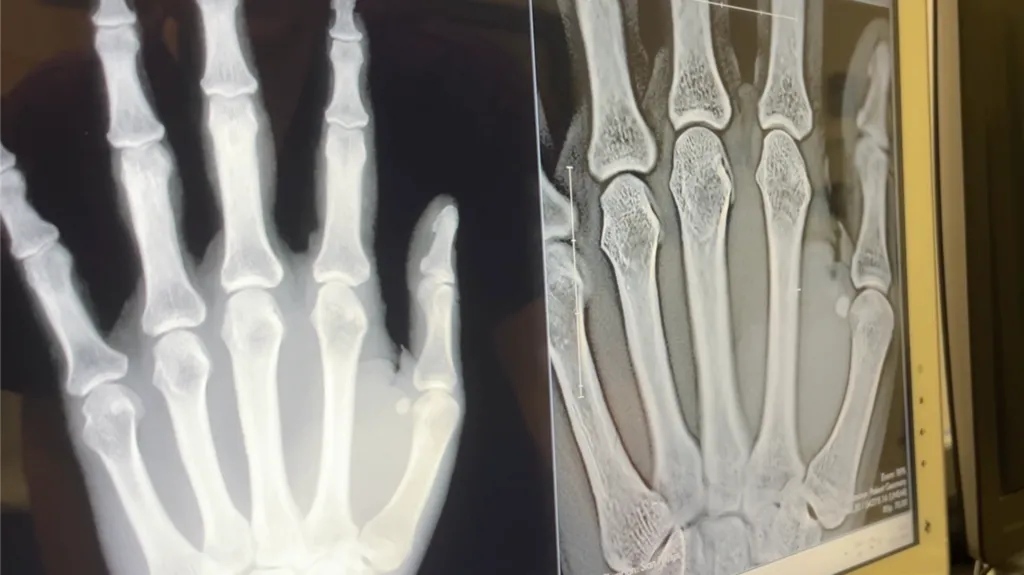

It is the first live trial of the portable imaging technology, which offers 3D imaging at a similar cost and radiation dose to traditional 2D X-rays, according to Karen Knapp, professor of musculoskeletal imaging at the University of Exeter.

It works by creating 3D images from a stack of image slices, much like CT and MRI imaging, but with a lower radiation dose compared to CT, faster imaging, lower power requirements and a compact size, she added.

Ms Knapp said up to 50% of people with early joint changes due to rheumatoid arthritis were missed when diagnosed using 2D X-rays.

She said: "We're really excited to be the first to trial the new Adaptix Ortho350, which promises much better visualisation of bone and joints than traditional 2D images.